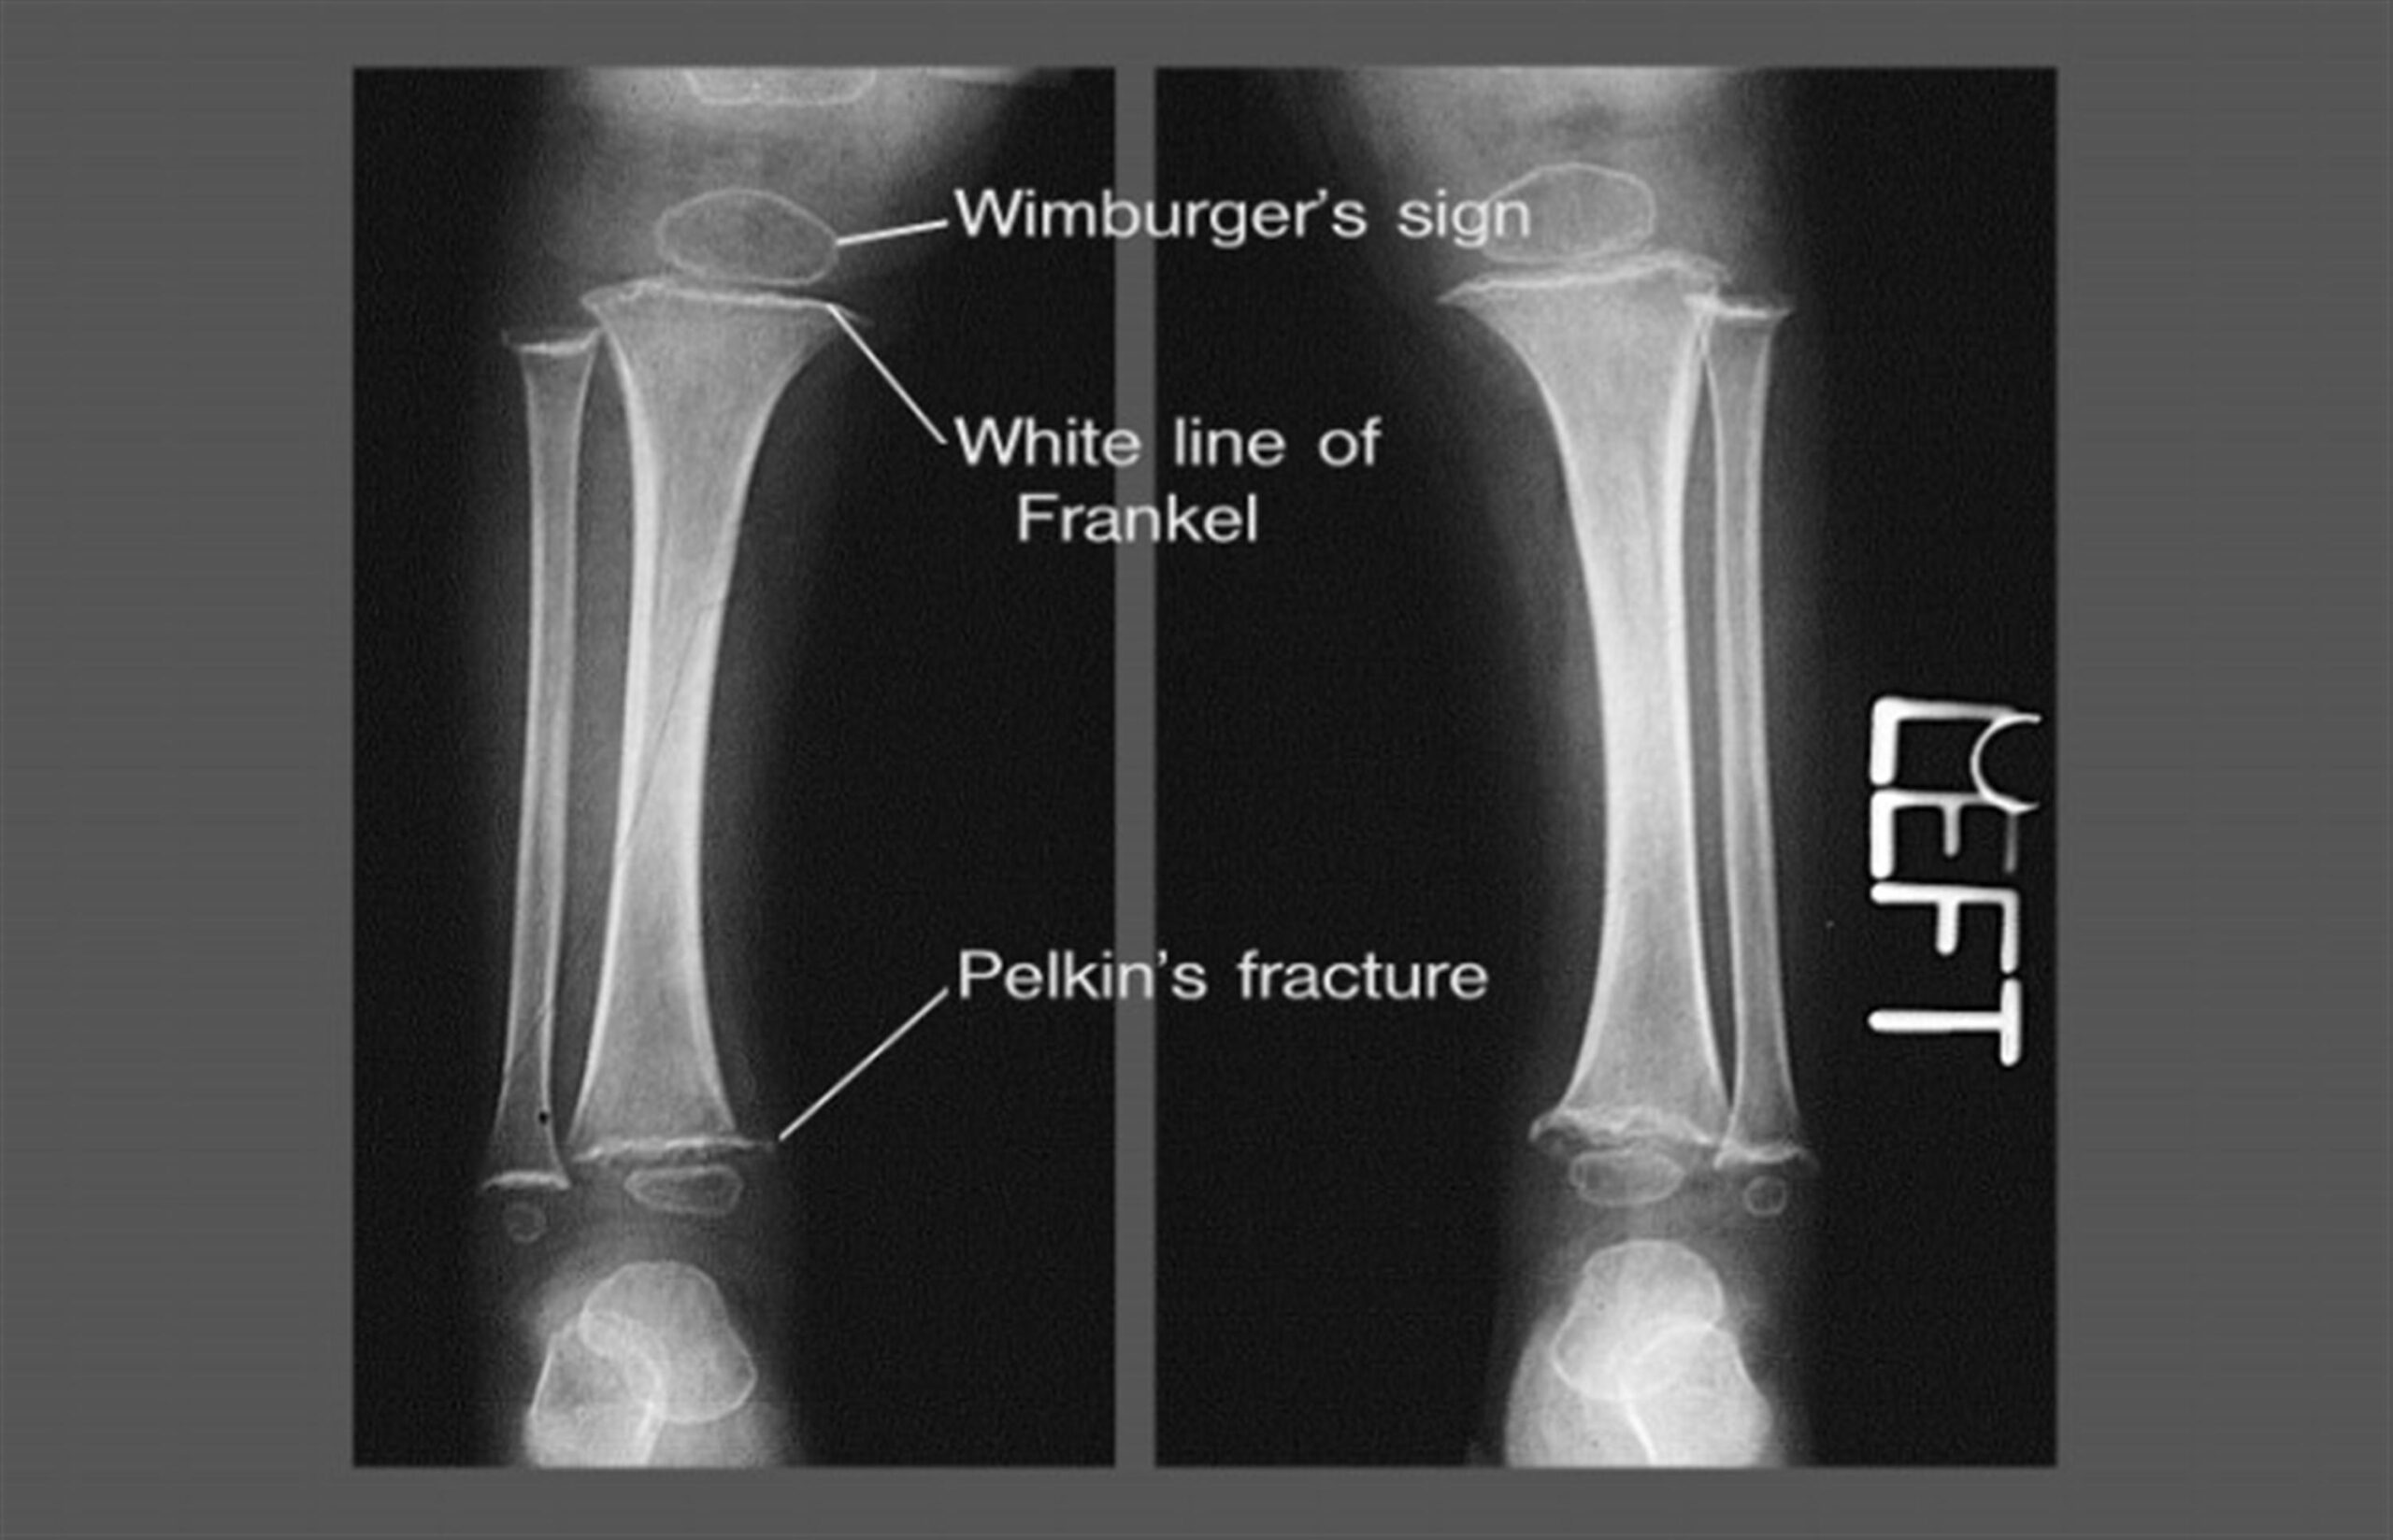

4. Bone manifestations: brittle, and fragile bones.On X-ray: white lines of Frankel (a dense band at the growing metaphyseal end, involving the provisional zone of calcification)